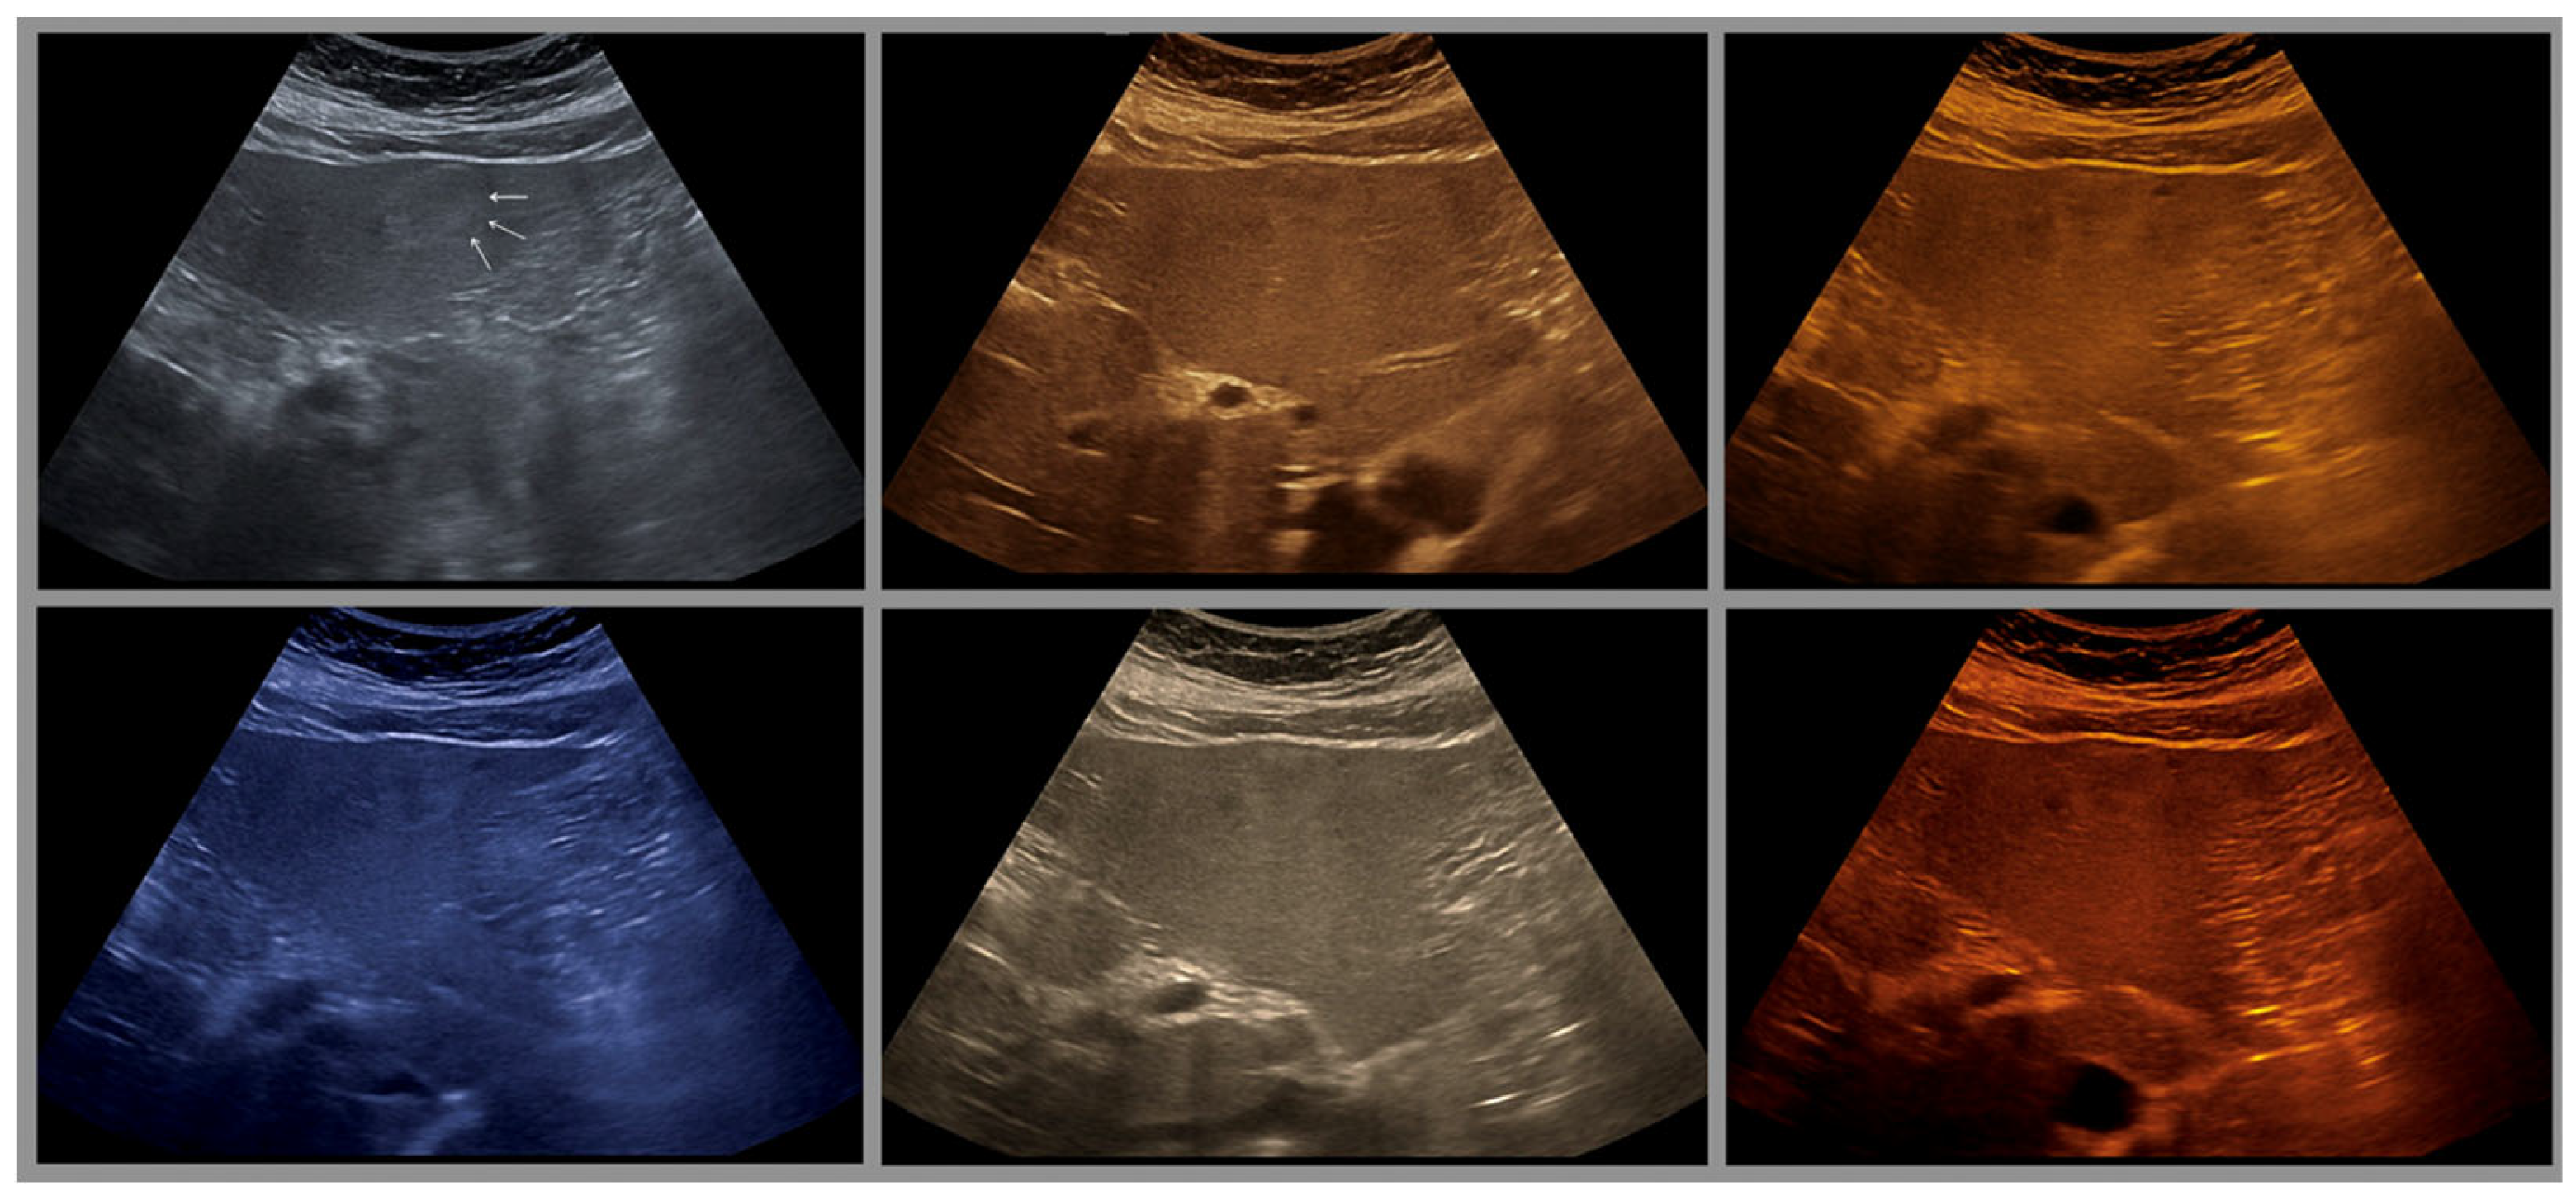

- The combination with speckle filters available in all high-end devices, similar to the low-pass filters used by Bleck et al. (1994) for tissue visualization [5], also yields significantly improved visualization results (Figure 5, Figure 6 and Figure 7). In principle, applications with new visualized texture analyses, such as random field models, are also conceivable [76,77].

- Merkel, D.; Brinkmann, E.; Kammer, J.C.; Kohler, M.; Wiens, D.; Derwahl, K.M. Comparison Between Various Color Spectra and Conventional Grayscale Imaging for Detection of Parenchymal Liver Lesions With B-Mode Sonography. J. Ultrasound Med. Off. J. Am. Inst. Ultrasound Med. 2015, 34, 1529–1534. [Google Scholar] [CrossRef]